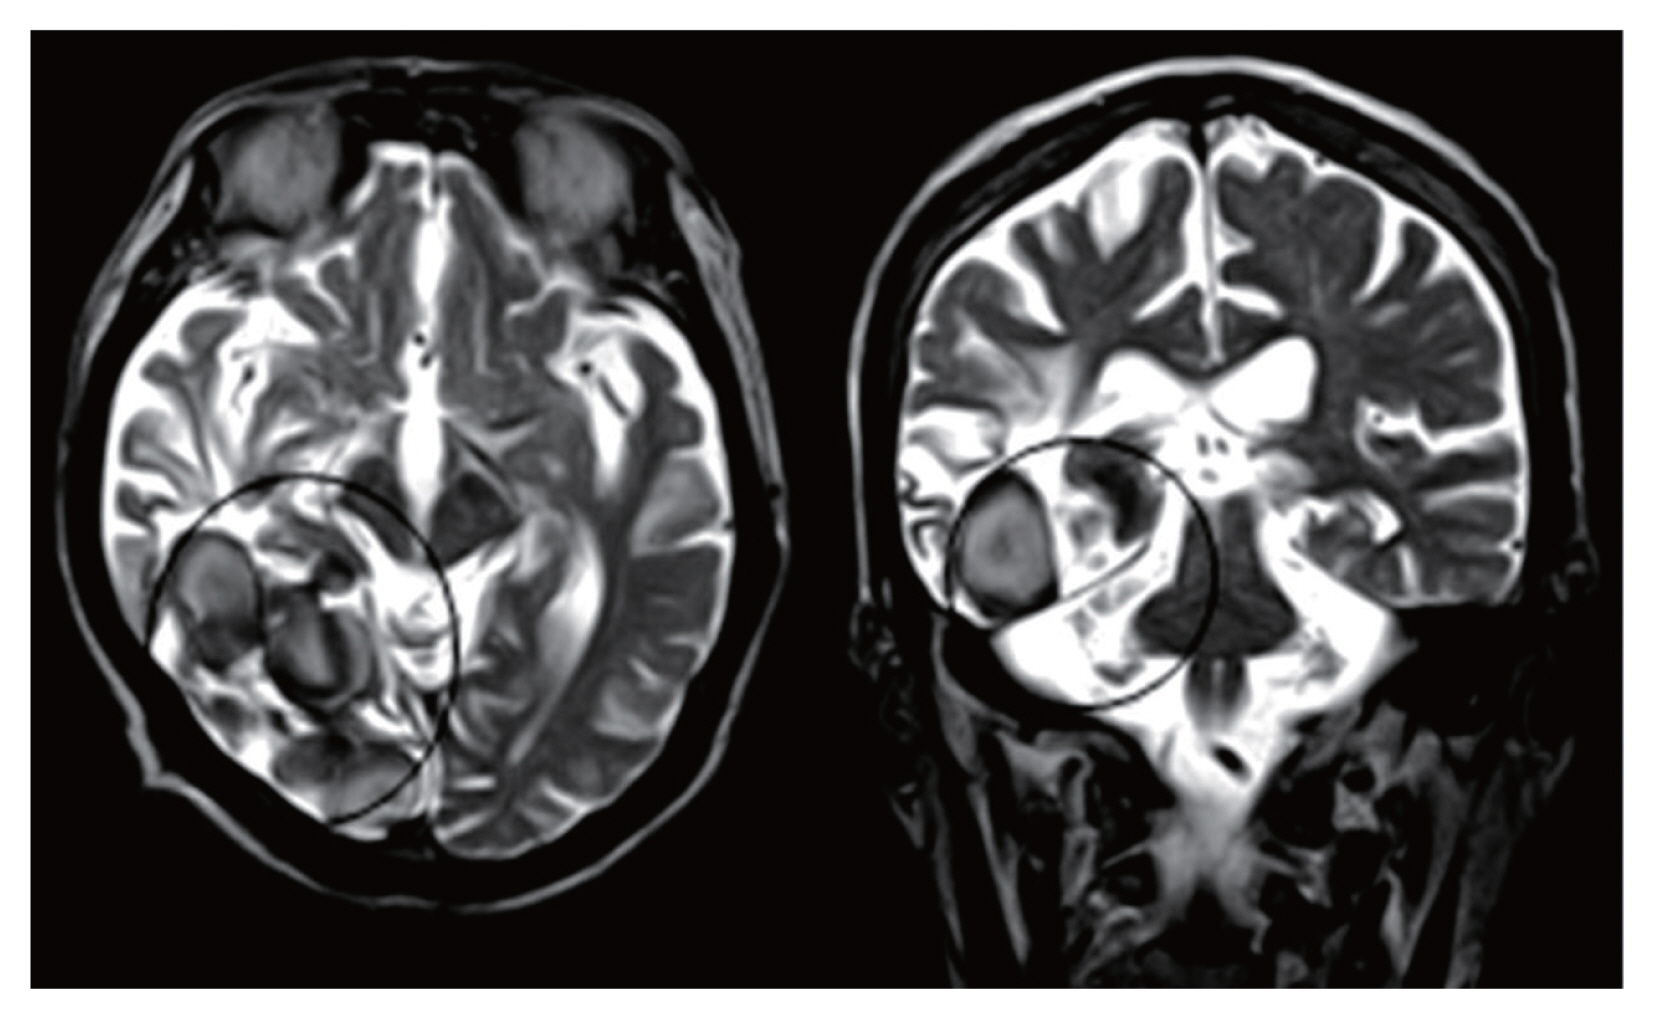

The neurological tests showed that the patient’s consciousness was clear. There were no findings of muscular anomalies. Motor and sensory functions were within normal range. However, the contrast-enhanced brain MRI revealed encephalomalacia in the right occipital and temporal lobes. Calcification and cystic lesions mainly in the right occipital lobe were also noticed (

Fig. 1). As the patient was suspected of having paragonimiasis or cysticercosis, specific IgG antibody levels against

In general, Alzheimer’s disease dementia shows moderate to severe atrophy of medial temporal lobe. However, this patient did not show prominent brain atrophy compared to those with similar ages, suggesting that the etiology of the patient’s dementia symptom might be more related to chronic cerebral paragonimiasis. This case showed that cerebral paragonimiasis of the right temporo-occipital areas could induce the dementia.

Fig. 1Horizontal (left) and coronal view (right) of brain MR image of an 80-year-old man who presented with dementia. Complicated cystic structures and calcifications (circles) are seen mainly in the right occipital lobe, with encephalomalasias in the right occipital and temporal lobes.